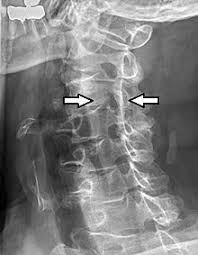

Nerve root pain is variably described as knifelike or aching and is widely distributed projecting to the sclerotome defined as deep structures such as muscles and bones innervated by the root. Lumbar Radiculopathy Nerve Root Compression Lumbar radiculopathy refers to disease involving the lumbar spinal nerve root. The Laser Spine Institute lists sciatica symptoms as pain numbness tingling and burning.

Lumbar radiculopathy is typically caused by a compression of the spinal nerve root. Typically root pain is aggravated by coughing sneezing and straining at stool actions that require a Valsalva maneuver and raise intraspinal pressure. Loss of strength reflex and sensation occurs in the territory of the compressed root. There is a significant volume of literature that would point to the neural tissues themselves as the most logical structures for future research that attempts to interfere with the natural history of this disease from the standpoint of pain. It is defined as sudden usually unilateral severebrief stabbing lancinating recurring pain in the distribution of one or more branches of the Vth cranial nerve Trigeminal neuralgia also known as prosopalgia or fothergills disease is aneuropathic disorder characterized by episodes of intense pain in the face originating from trigeminal nerve. Herniated disc causing a single nerve root compression leg pain back pain. An estimated 20 million Americans suffer from peripheral nerve damage aka.